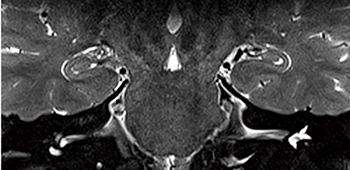

VEバージョンソフトウエアに搭載されるAdvanced WARPは,WARP法とVAT法の撮像シーケンスに加えて,SEMAC法を搭載することにより,撮像スライス面内・方向へのメタルアーチファクトの低減が可能になった。各関節のインプラント撮像に対して,最適な撮像収集バンド幅の調整・設定に加えて,撮像スライス方向に対するリードアウト・エンコード傾斜磁場の最適な印加による信号の位置情報の補正が可能になった(TSEシーケンス)。Advanced WARPによって,撮像スライス面内・方向に対してのメタルアーチファクトの低減を可能にした。

これにより,インプラントそのものは無信号で描出されることに変わりないが,従来法のようにメタルアーチファクトで診断ができないという状況は,大きく改善できると思われる。Advanced WARPの利用によって,術後のインプラント埋入部周辺組織の炎症などの診断において,より高精細に診断できることが期待できる(図4)。

図4 従来法とAdvanced WARPの比較画像例